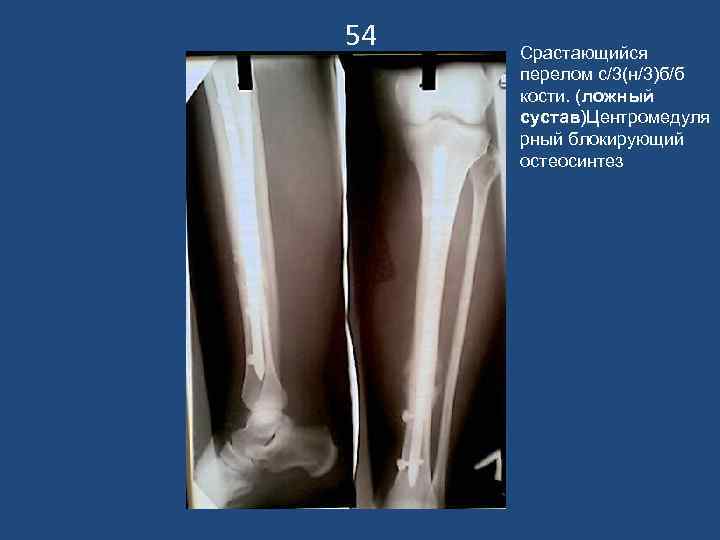

54 Срастающийся перелом с/3(н/3)б/б кости. (ложный сустав)Центромедуля рный блокирующий остеосинтез